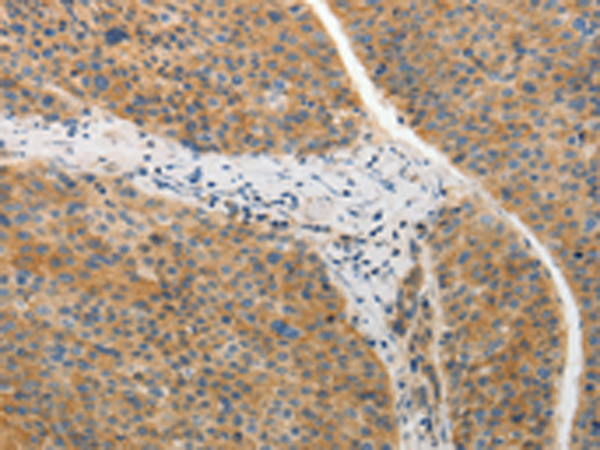

IHC positive control: |

Human liver cancer and Human lung cancer |

IHC Recommend dilution: |

25-100 |